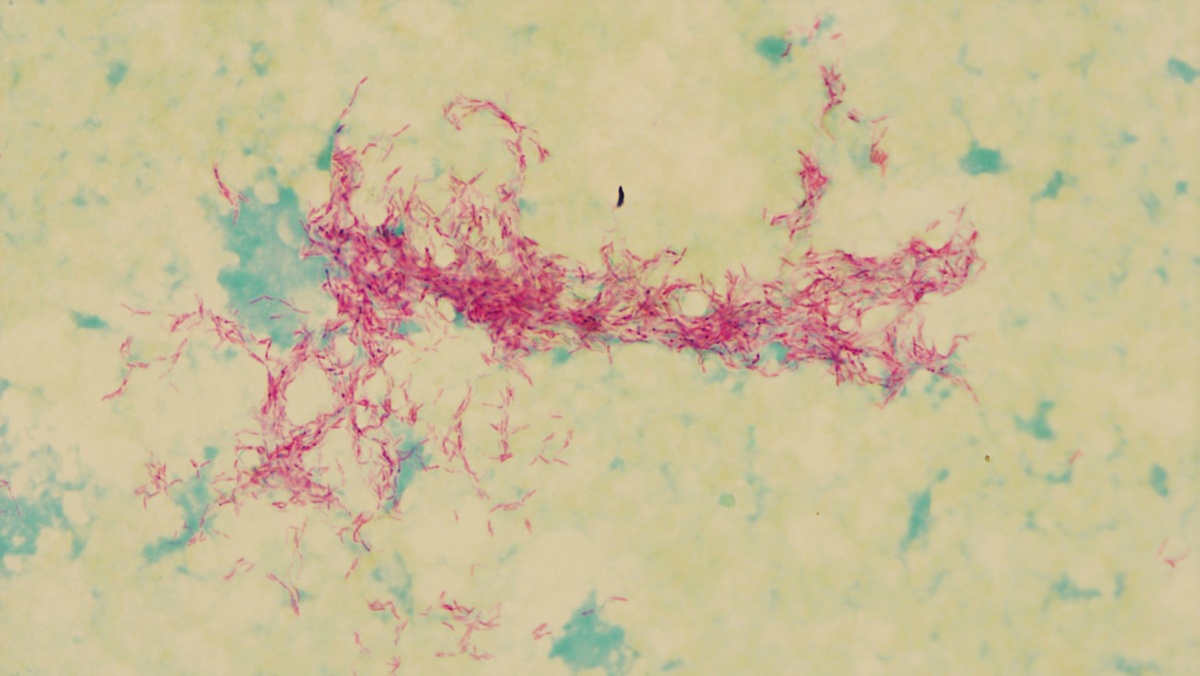

Чаще всего туберкулёз поражает лёгкие: на лёгочную форму приходится около 95% всех случаев заболевания. У мужчин на втором месте по распространённости — туберкулёз костей и суставов, у женщин — поражение органов мочеполовой системы. При подозрении на болезнь пациенту назначают рентген грудной клетки, общий анализ крови, пробу Манту и исследование мокроты на микобактерии.

Фото: из открытых источников